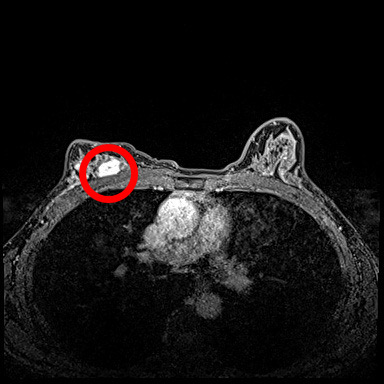

目前新式乳房微創手術有整形式乳房保留手術、內視鏡乳房切除合併重建手術等兩種術式,張群明醫師指出,術後的兩側乳房看起來不會有明顯差別,其中「內視鏡乳房切除合併重建手術」從胸部的側邊接近腋下處打開一個約五公分的傷口,將整個乳房組織取出後,放置義乳重建。適合乳房小、腫瘤小且沒有腋下淋巴結轉移的患者。林小姐身材較嬌小,乳房大小為中等偏小,且腫瘤小於兩公分,因此建議治療方式為內視鏡乳房切除合併重建手術。

乳癌目前依據荷爾蒙受體(雌激素受體,黃體激素受體)與HER2受體,分成三種型態:荷爾蒙受體陽性、HER2受體陽性、三陰性乳癌。林小姐是第一期乳癌,荷爾蒙受體陽性,沒有淋巴結轉移,張群明醫師說,除了為林小姐手術外,再加上口服抗荷爾蒙藥物治療,定期服藥追蹤即可。張群明醫師也提到,現今乳癌治療成績來越來越好,醫療團隊會依照患者的年齡、身體狀況、乳癌不同的受體型態、腫瘤大小、淋巴結有沒有轉移等等,來訂定最適合的治療計畫,目前第一期乳癌五年的平均存活率超過95%;第二期乳癌,平均活率也接近90%;第三期的平均存活率約70%;第四期約25%,只要早期發現,早期治療就有很好的治療結果。